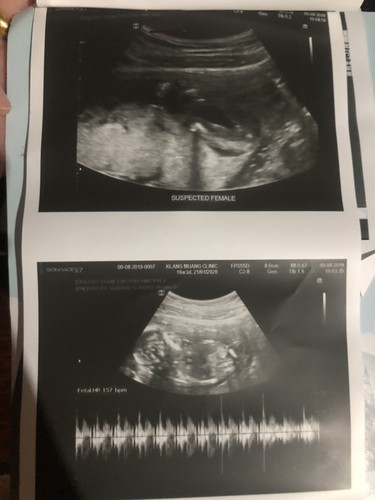

ช่วยดูรูปนี้ให้หน่อยคะ ว่าคือส่วนไหนของน้อง

หมอบอกเราว่า 60-70% เป็น ผญ รูปนี้พอจะดูออกไหมคะ ว่าน้องเป็น ผญ หรือ ผช

รูป1 ส่วนก้น/หว่างขา ผญ.จ้า รูป2 ส่วนหัว+ลำตัว ซูมจากด้านหลัง เหมือนน้องนอนตะแคงให้อยู่ค่ะ

รูปแรก หว่างขาน้องค่ะ ไม่มีอะไรโผล่ขึ้นมาจร้า น่าจะหญิง

ผู้หญิงค่ะ

ผู้หญิงจ้า